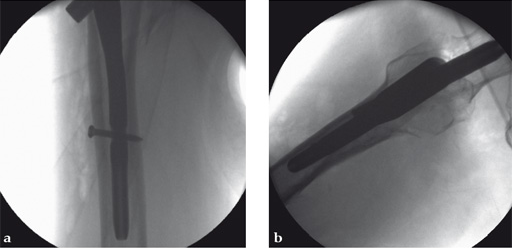

d In AP projection the tip of the blade should be positioned in the center of the femoral head, in lateral projection the blade should run parallel to and in middle of the neck and also end dead center of the femoral head. The distance of the tip of the blade to the joint should be approximately 10 mm. No predrilling is recommended in osteoporotic bone.

Case 3:

Compression feature used intraoperatively.

Case provided by Michael Blauth, Innsbruck, Austria